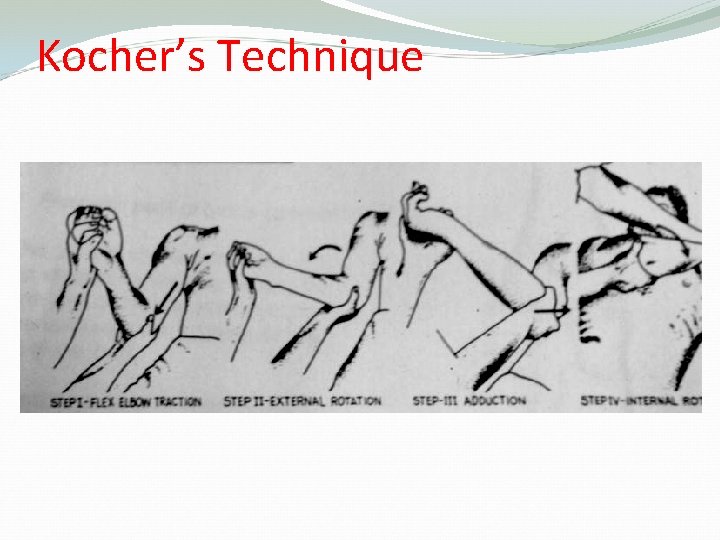

Methods of Reduction of anterior shoulder Dislocation Hippocrates Method ( A form of anesthesia or pain abolishing is required ) Stimpson’s technique ( some sedation and analgesia are used but No anesthesia is required ) Kocher’s technique is the method used in hospitals under general anesthesia and muscle relaxation

Kocher’s Technique